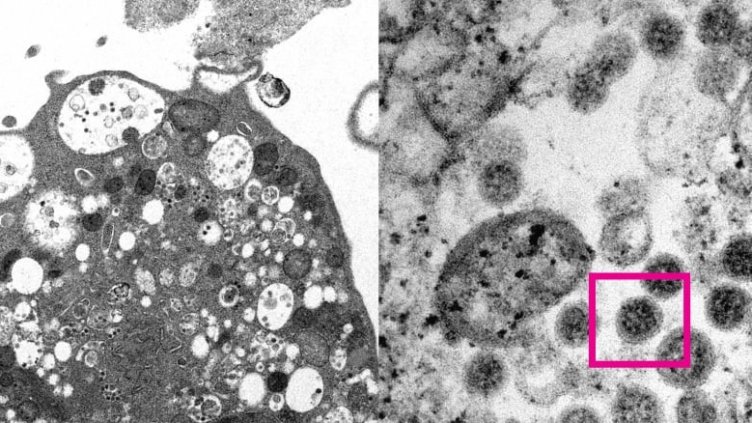

Снимка: CBC

Подвариантът BA.2 на разновидността Омикрон на новия коронавирус е по-силно заразен от "основния" BA.1 и по-способен да се разпространява сред ваксинирани хора, установи датско изследване, цитирано от Ройтерс.

Изследването е показало, че BA.2 сравнително по-често от BA.1 заразява напълно ваксинирани и хора с бустерни дози ваксини, което е знак за "имуно-инвазивните свойства" на подварианта.